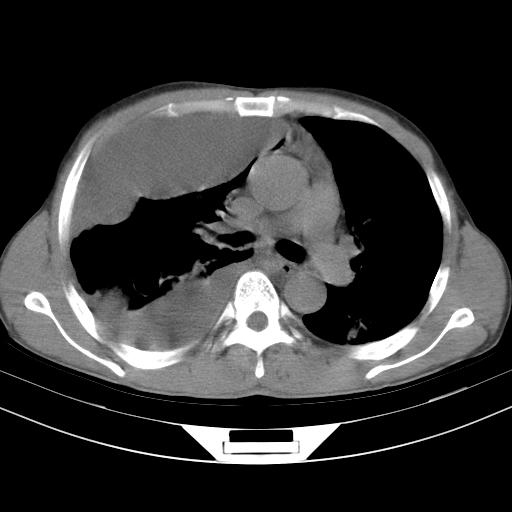

男性,44岁,结核病史多年。现胸闷气短,咳嗽,偶咳血。

1)两肺继发性肺结核伴空洞形成,左肺多发性结核球。2)右侧大量胸腔积液伴右肺部分膨胀不全。3)纵隔淋巴结肿大。

支持1)两肺继发性肺结核伴空洞形成。2)右侧大量胸腔积液伴右肺部分膨胀不全。3)纵隔淋巴结肿大。

吉大一院胸水抽检结果:结核性胸水